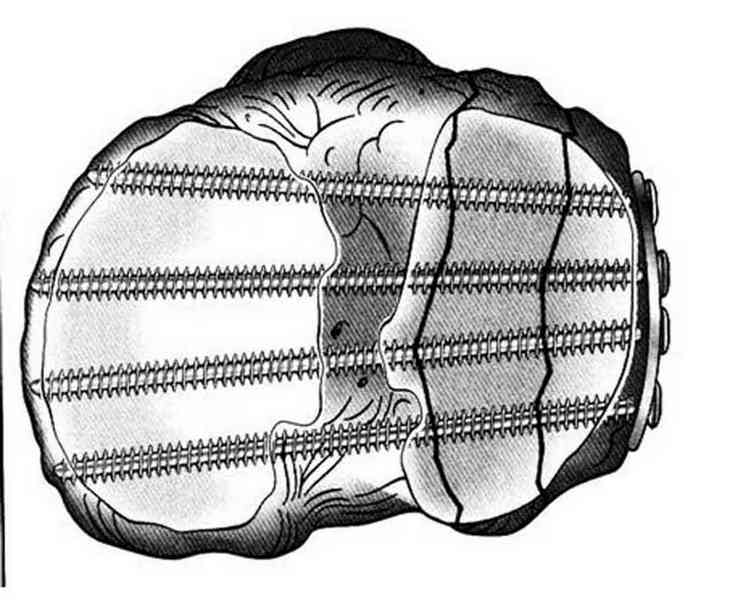

Основная задача в лечении околосуставных переломов является создание

солидного базиса в субхондральной зоне. Пластина подпорка (Butress)

или субхондральные перкутанные шурупы в виде плота (Raft) для ранних

движении.

Имя     : 10 raft technique.jpg

Тип     : image/jpeg

Размер  : 55979 байтов

Описание: отсутствует

Url     : http://weborto.net:8080/pipermail/ortho/attachments/20100926/dbcec959/attachment-0021.jpg